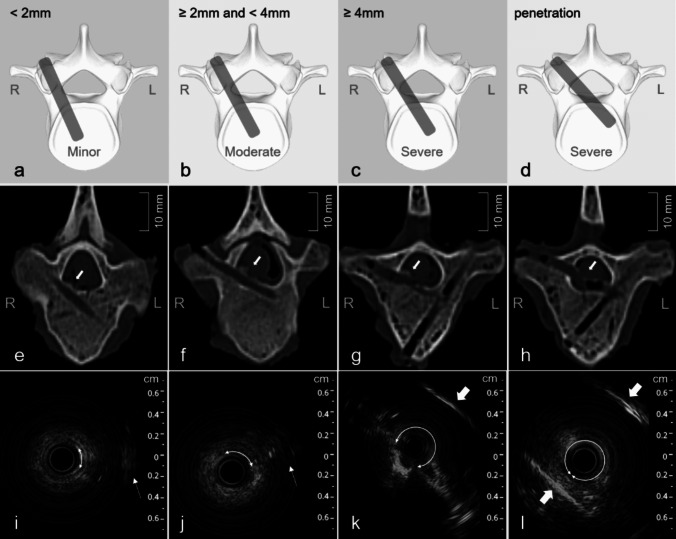

The degree of malposition of the pedicle screw holes were classified used the 2 mm increment according to the extent of screw hole deviation shown in CT images [1, 6]: (1) Correct position, if the screw hole is completely within the pedicle and there is no cortex damage; (2) Minor malposition, if the screw hole deviation is < 2 mm (Fig. 4a); (3) Moderate malposition, if the screw hole deviation is ≥ 2 mm but < 4 mm (Fig. 4b); (4) Severe malposition, if the screw hole deviation is ≥ 4 mm (Fig. 4c) or the cortex is penetrated causing the screw hole entirely inside the spinal canal (Fig. 4d). The clinical significance of more than 2 mm deviation lies in the fact that an intraoperative correction of the screw hole trajectory or screw revision should be required.

Fig. 4.

From top to bottom, the schematic, CT, and EUS images of different degrees of pedicle screw hole malposition are shown, respectively. From left to right, the degree of malposition is minor, moderate, severe without penetration, and severe with penetration. The white arrows within the image (e) to (h) point to the breaches of screw holes. The arcs with arrows at both ends indicate the absent range of the screw hole wall. The white thin arrows indicate echoes from the tissues out of the hole in the image (i) and (j), and the white thick arrows indicate the walls of the spinal canal in the image (k) and (l)

In the 76 pedicle screw holes, CT reveal that there were 13 holes (17.11%) with correct position, while there were a total of 63 holes (82.89%) with malposition. Among the misplaced holes, there were 9 holes (11.84%) with minor malposition, 9 holes (11.84%) with moderate malposition, 45 holes (59.21%) with severe malposition (Including 35 holes where the spinal canal was penetrated) (Fig. 4e-h).

Against the grading criteria of screw hole malposition based on CT, the ultrasound findings were as follows: (1) When the position of the screw hole was correct and entirely within the pedicles, the echo around the hole appeared as an intact wide ring-like structure composed of diffused coarse speckles with medium intensity, and the average ring width was of about 2 mm (Figs. 3c and 5b-h). (2) When the malposition of the hole was minor to moderate, the site of damaged cortex in the wide ring structure showed the focal deformation or absence accompanied by varying degrees of echo from surrounding tissues (Fig. 4 i, j). However, the damaged area may sometimes also show a slightly enhanced echoes. (3) In the images with severe screw hole malposition, the ultrasound presentation is characterized by the absence of the most of the wide ring, even the disappearance of the echo of the spinal canal wall on the same side, accompanied by the appearance of the echo of the spinal canal wall on the opposite side (Figs. 4k and 5m-p). (4) When the screw holes completely penetrate through the pedicle cortex into the spinal canal, the ultrasound images manifest as the whole loss of wide ring echo, replaced by linear, high-intensity echoes from the walls of the spinal canal on both sides of the screw hole (Fig. 4 l).